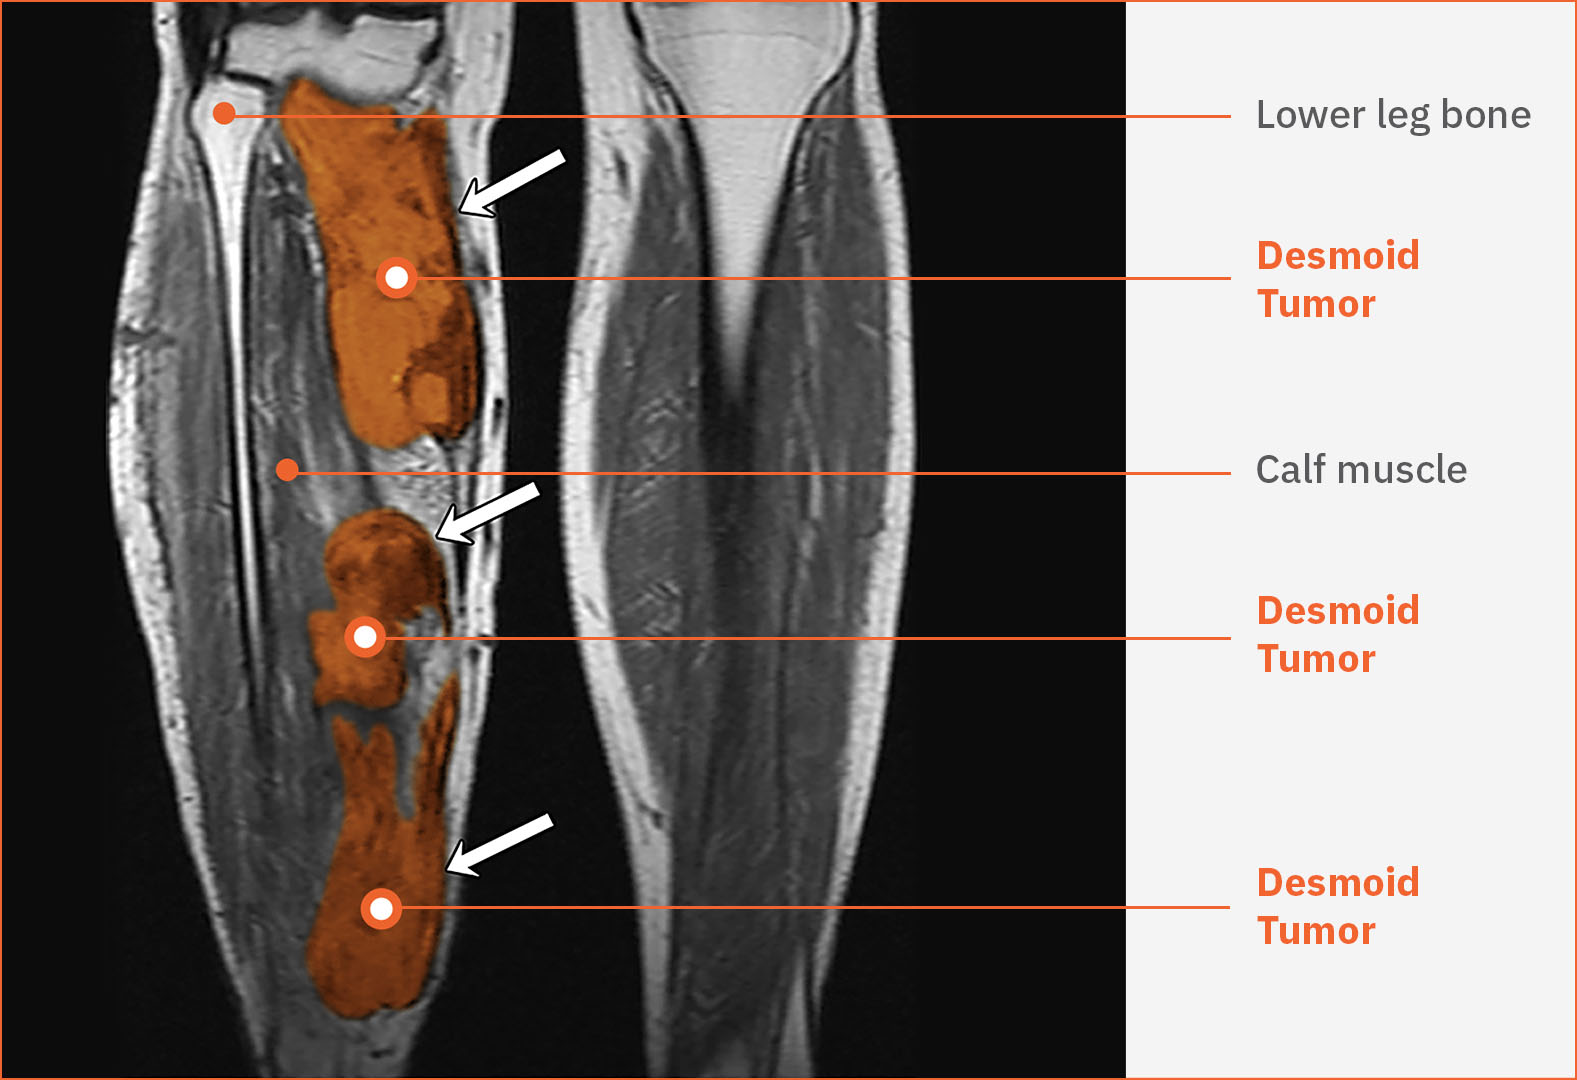

From www.desmoidtumors.com

What is a desmoid tumor? Springworks House Leg Tumor — sts tumors can occur anywhere in the body, but more than half develop in a person’s arm or leg. Soft tissue sarcomas are rare. — house's leg injury was caused by an infarction while golfing, leading to severe pain and a dependency on vicodin. Towards the end of season 7 house took an. What is soft tissue. House Leg Tumor.